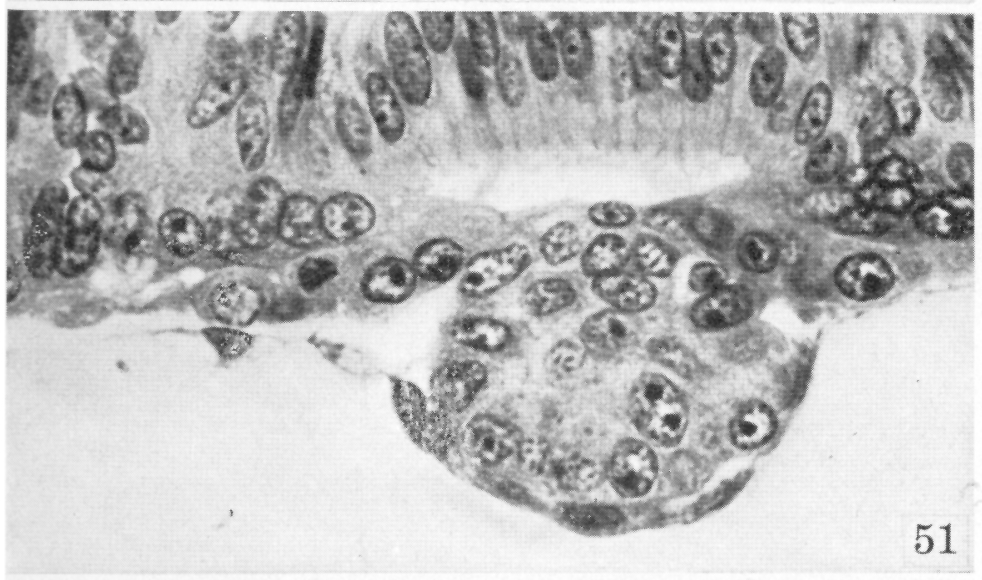

Fig. 51.

Heuser and Streeter, 1941

.